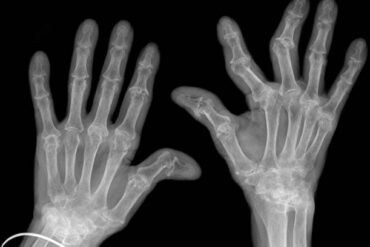

Causes of Varicose Veins: Varicose veins occur when veins become enlarged and twisted due to weakened vein walls and valves. Several factors contribute to their development:

- Visible Enlarged Veins: Twisted, bulging veins on the legs and feet are a characteristic sign of varicose veins.

Untreated varicose veins can lead to complications such as superficial thrombophlebitis (inflammation of a vein), bleeding, and venous ulcers (open sores). Additionally, varicose veins can impact self-esteem and body image due to their appearance.